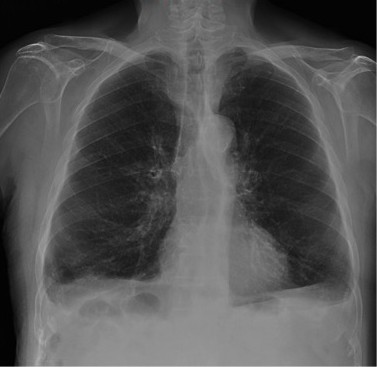

Empecemos, ¿qué ves?

- Comprobar que la placa está bien centrada e inspirada (6 arcos costales anteriores ó 9 posteriores).

- Abdomen y Diafragma

- Partes blandas y estructura ósea.

- Mediastino con silueta cardiaca.

- Parénquimas pulmonares (por separado)

- Comparar un pulmón con otro.

Seguir esta sistemática, dejando el pulmón para el final no nos olvidaremos de lo más importante.

Regla: Acaso Tiene Mucha Patología Pulmonar (Abdomen, Tejidos blandos y hueso, Mediastino, Pulmón por separado, Pulmón bilateral)

Nota: ¡¡¡No olvidar la placa lateral!!! La regla a seguir es la misma. Leer abdomen y diafragma, examinar parte posterior, tejidos blandos y subir por la columna; tráquea y descender por mediastino. Finalmente pulmones.

Solución: Es un estudio Normal. Silueta cardiomediastínica y parénquimas pulmonares sin alteraciones significativas.